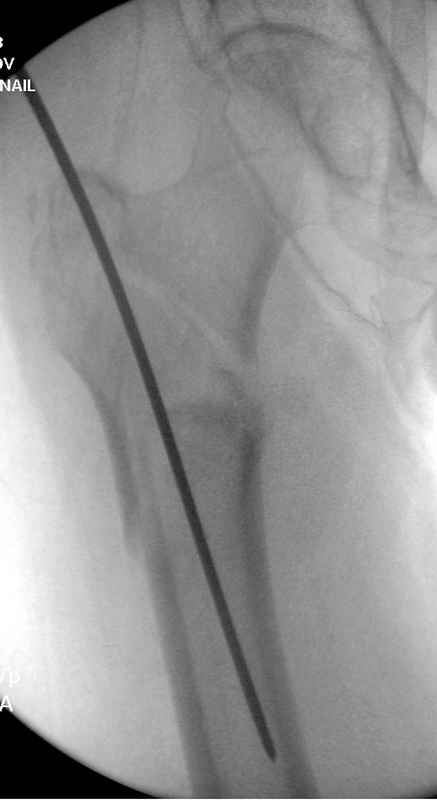

Re: Чрезвертельный перелом бедра

Здесь 83 года, травма в результате падения